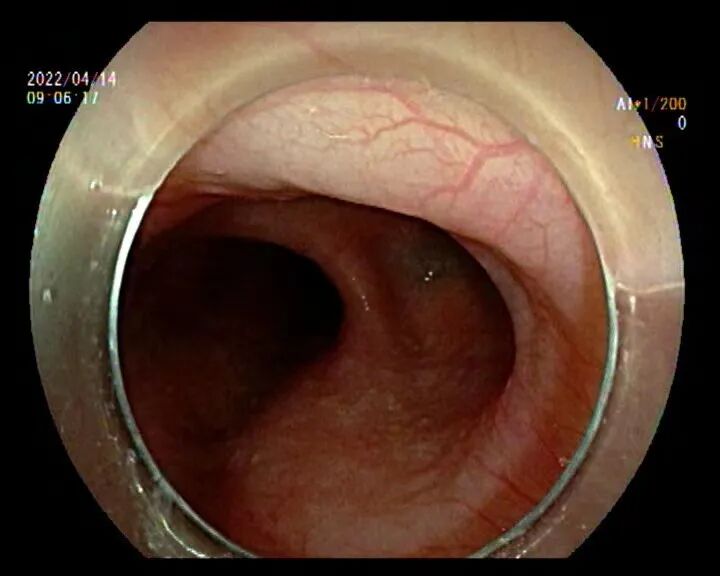

住院后医生为她安排了胃镜检查和上消化道钡剂造影,检查结果提示贲门失弛缓及食管中段憩室。

韩梅病情特殊,消化内科主任李滨教授和副主任肖绪华在详细阅读各项检查报告后,发现患者食管下端呈“鸟嘴样”改变,同时上端分别紧接一个约2.5cm大小的憩室,结合患者病史,明确患者“贲门失弛缓合并食管中段憩室”的诊断。他们认为造成了韩梅多年梗噎和反流的病的原因是:食管下段肌群持续紧缩,蓄积的食物被迫推向多发的憩室,加重憩室的扩张,食管及憩室内食物反流。

胃镜图(左图食管下段扩张,右图食管中段憩室)